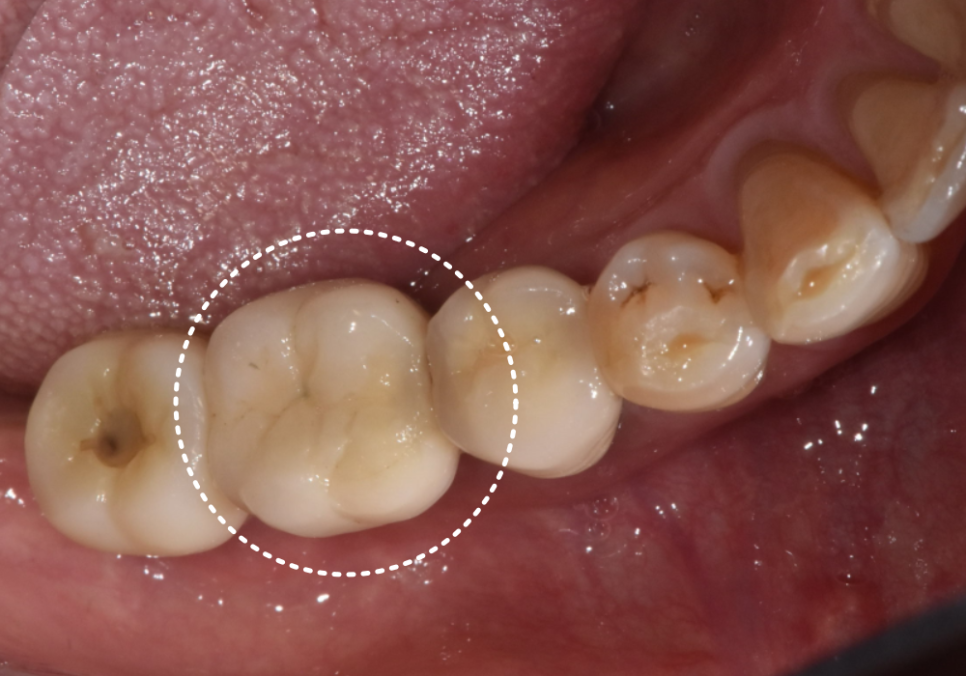

이번에 오신 환자분은 꽤 오래전,

타 치과에서 임플란트를 하셨던 분입니다.

그동안은 아주 편안하게 잘 사용하셨다고 해요.

그런데 어느 날부턴가 조금씩 흔들리더니,

급기야 손으로 건드리면

'끄덕'하고 움직이는 지경까지 오게 되셨죠.

정확한 원인을 찾기 위해

엑스레이부터 찍어보았습니다.